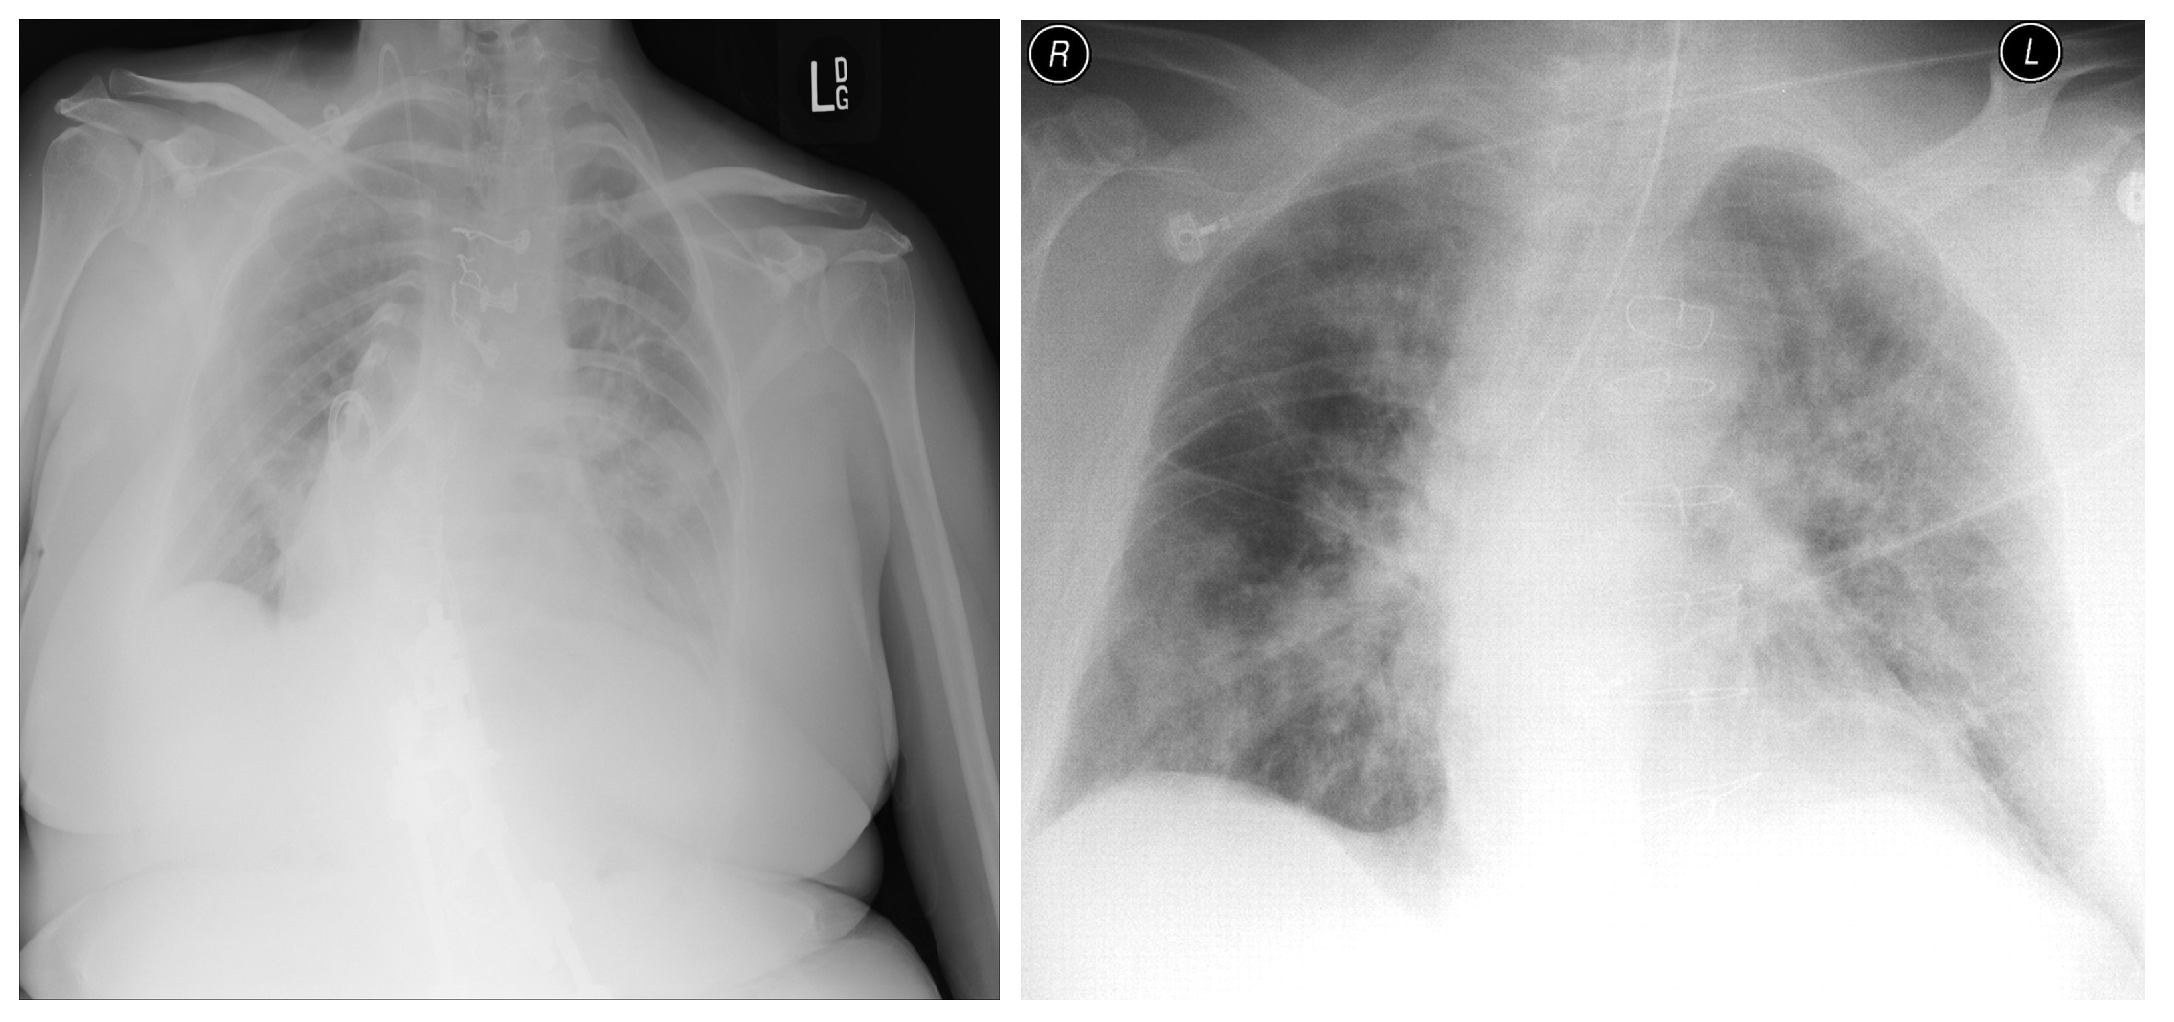

4.5. Explainability

- Selvaraju, R.R.; Cogswell, M.; Das, A.; Vedantam, R.; Parikh, D.; Batra, D. Grad-cam: Visual explanations from deep networks via gradient-based localization. In Proceedings of the IEEE International Conference on Computer Vision, Venice, Italy, 22–29 October 2017; pp. 618–626. [Google Scholar]

- Panwar, H.; Gupta, P.; Siddiqui, M.K.; Morales-Menendez, R.; Bhardwaj, P.; Singh, V. A deep learning and grad-CAM based color visualization approach for fast detection of COVID-19 cases using chest X-ray and CT-Scan images. Chaos Solitons Fractals 2020, 140, 110190. [Google Scholar] [CrossRef] [PubMed]